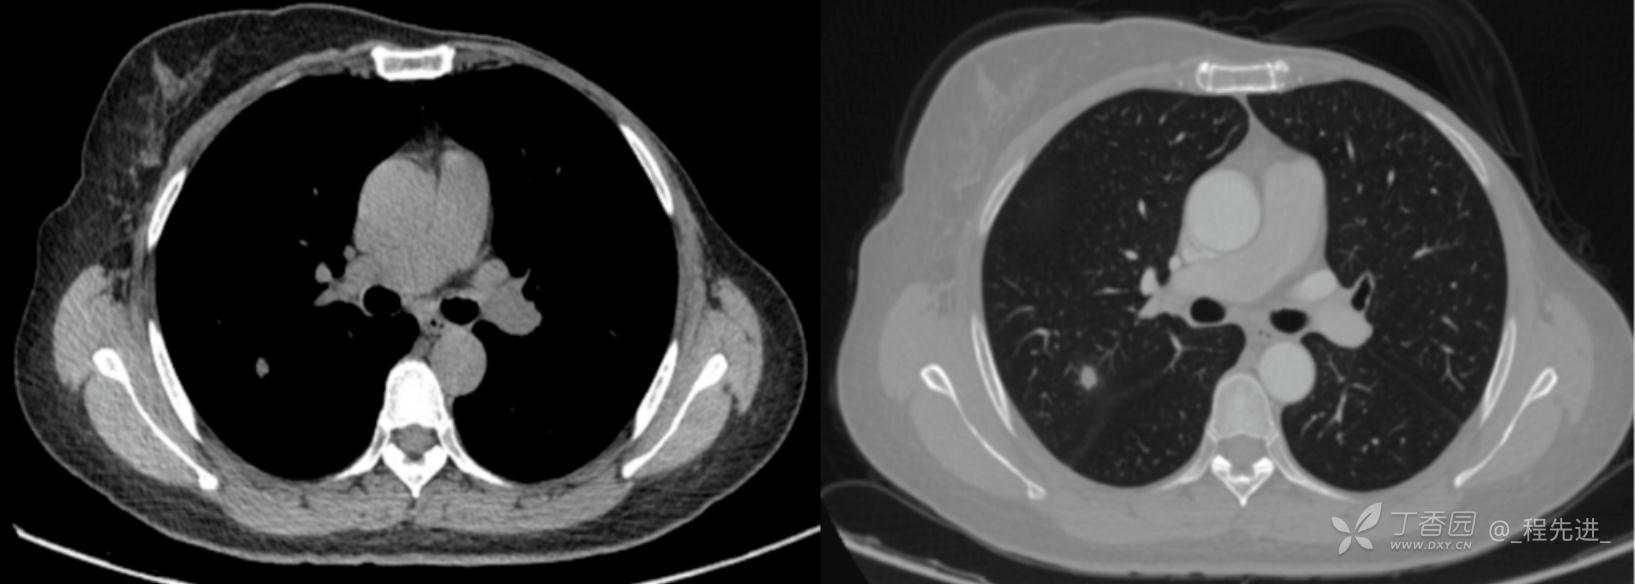

患者性别:女

患者年龄:52岁

简要病史:体检发现右肺上叶结节

既往史:左乳腺癌术后,化疗后